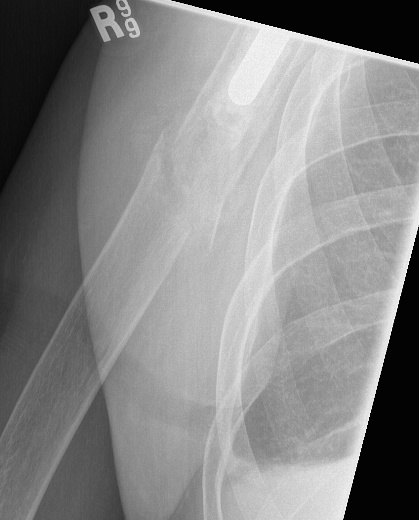

TSR Periprosthetic FractureTSR Periprosthetic Fracture